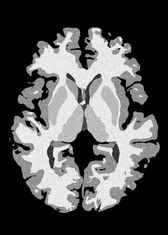

4.2 Registration to a 100 micron ex-vivo brain MRI volume

To showcase the efficacy of our method on real large scale images, we register a 250 in-vivo MRI image (Lüsebrink et al., 2017) to a 100 ex-vivo FLASH human brain volume (Edlow et al., 2019). This represents an inverse problem with more than 11.2B optimizable parameters (compared to 20M for clinical datasets), or 44.8GB of GPU memory. The entire problem does not fit on most GPUs, necessitating distributed multimodal registration. We optimize a composite transform - affine followed by a diffeomorphic mapping; details can be found in Section E.1. Multimodal deformable registration took 58 seconds on 8 NVIDIA A6000 GPUs, which is unprecedented at this resolution. Fig. 6 shows qualitative results, highlighting the ability to register highly detailed structures such as cerebellar white matter; these structures are not visible at macroscopic scales. The resultant advantages of performing registration at this scale can allow researchers to characterize the neuroanatomy at microscopic resolutions and allow morphometric analysis of cortical layers and subcortical nuclei among other structures.